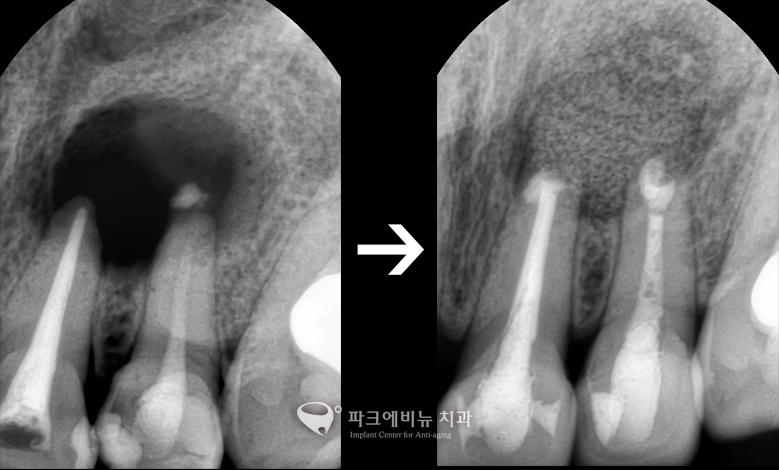

* 충치신경치료를 여러 번 해도 낫지 않는 뿌리 끝 염증! 어떻게 할까?

치근단절제술

치수에 염증이 있거나, 세균에 감염이 되어 치아 뿌리 끝에 염증이 생긴 경우 근관 치료를 시행 한 후 치아 뿌리 끝 주변의 조직들은 치료가 되지 않는 경우가 많다. 이럴 경우, 치아 뿌리 끝에 있는 치조골 주변의 염증 조직을 치아 뿌리 끝 부분을 잘라내게 되는 수술이다. 이 수술을 받는다면, 치아를 뽑지 않고 보존을 시킬 수 있다는 장점이 있다. 근관 치료는 치수에 염증이 있거나 세균에 감염이 되었을 때 손상된 치수를 제거하는 방법이다. 이 수술 후 제거된 치아 뿌리 끝 중심부에 구멍을 낸 후 충전물을 채워 완전히 막는다. 염증 부위가 넓을 경우에는 뼈가 잘 형성이 되도록 약을 넣어주기도 하고, 수술한 부위를 봉합하고 수개월이 지나게 된다면 치아 뿌리 주변에 뼈가 차게 된다. 때로는 염증 부위가 커서 골 소실 양이 많은 경우 뼈 이식을 통해 보강을 할 수도 있다.